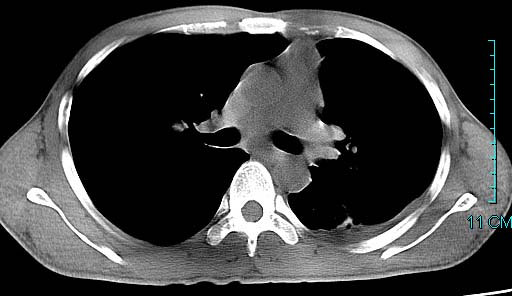

以下是引用ctkz987在2006-3-28 13:04:00的发言:[br]左侧胸腔积液穿刺后多发气液平(多房性),结合临床有高热不除外合并感染。

以下是引用qian在2006-3-28 14:32:00的发言:[br]左肺下叶大片状阴影,密度不均,见有条片影和空洞及气液平,少量胸腔积液伴有胸膜增厚,从图像看积液密度比水的密度高,结合病史,考虑左下肺化脓性炎症伴有脓胸。

以下是引用wawaquan在2006-3-28 22:25:00的发言:[br]左上肺舌段多发斑片影。结合“男24y咳嗽咳痰气促伴高热(38.5--39.5)20多天”及穿刺史,[br]考虑1 左下肺化脓性炎症;2脓胸。

以下是引用乡医在2006-3-28 18:37:00的发言:[br]左侧多发液气平面结合患者男24y咳嗽咳痰气促伴高热(38.5--39.5)20多天,查胸水:ldh239.3,总蛋白59.19,tb-ab阴性,利凡它试验+,红c2.7*109,白c1.08*109,分类淋巴92%分叶8%,考虑1脓胸2肺隔离征感染